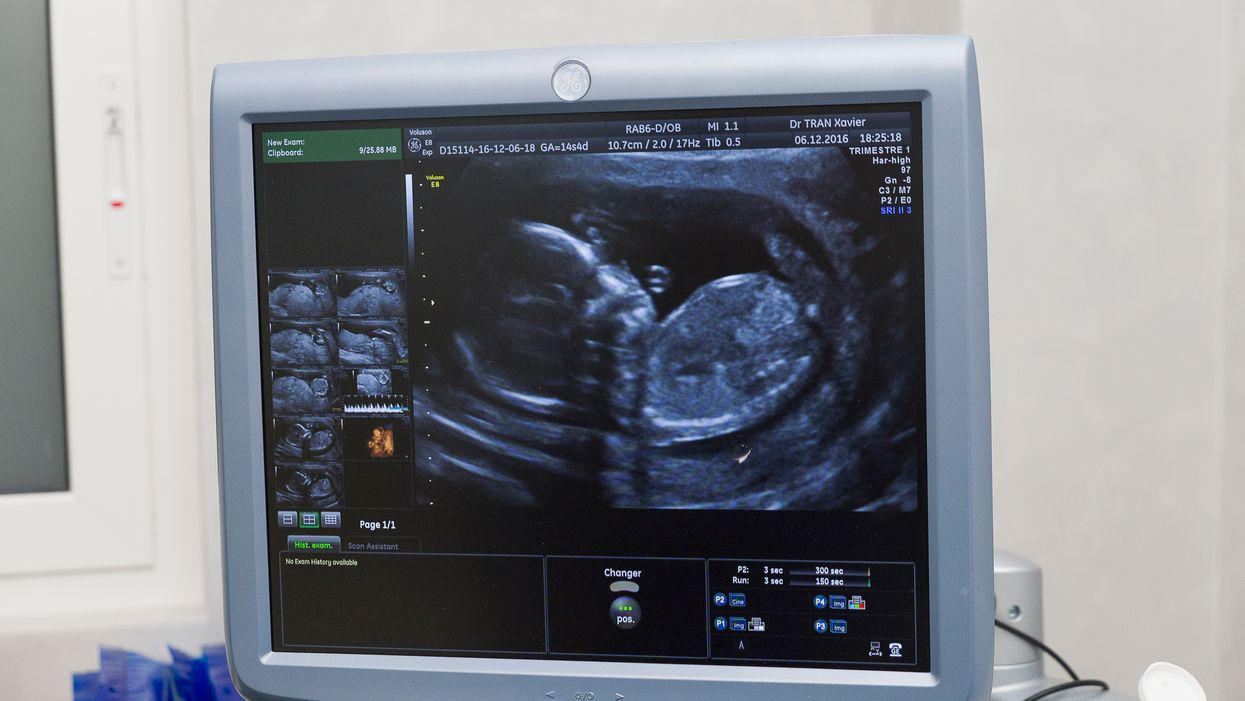

At 20 weeks, which is exactly halfway through an average pregnancy, a baby is about 6 1/2-inches long.